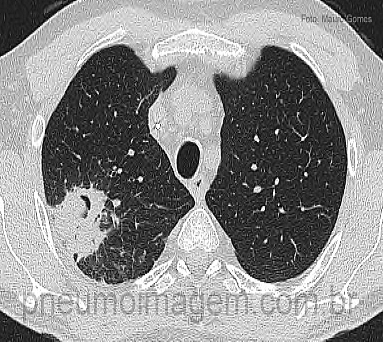

As infecções fúngicas possuem incidência e importância crescentes em imunocomprometidos e imunocompetentes e o diagnóstico oportuno baseia-se no uso apropriado dos testes laboratóriais.

A American Thoracic Society publicou novas recomendações para o diagnóstico rápido e preciso das infecções fúngicas.Esta diretriz inclui recomendações específicas sobre o uso do teste da galactomanana no soro e no LBA para o diagnóstico de

aspergilose pulmonar invasiva, o papel da PCR no diagnóstico de

aspergilose pulmonar invasiva, o papel dos ensaios de b-D-glucana no diagnóstico de candidíase invasiva e a aplicação de sorologia e

teste antigênico no diagnóstico das micoses endêmicas.